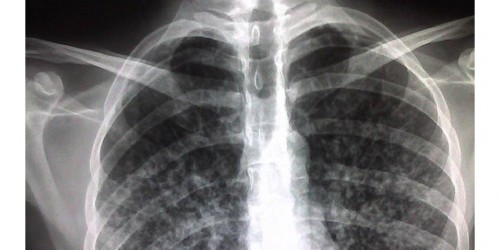

Hello, folks. My daughter is diagnosed with XDR-TB tuberculosis. I must admit that this is quite new piece of info for me. I would like to know something more about this and how serious it is. I would really appreciate all your replies considering this. Thank you in advance. Bye, folks.

Hi, there. XDR-TB stands for extensively drug resistant tuberculosis. This form means that tuberculosis is resistant to rifampicin and isoniazid from the first line of drugs, as well to quinolone family and other drugs from the second line of drugs. The treatment option is much reduced. This is a very serious form of tuberculosis. Your daughter should also do the HIV test. I hope she will be all right. Please, let me know how she is doing. Good luck! Bye!